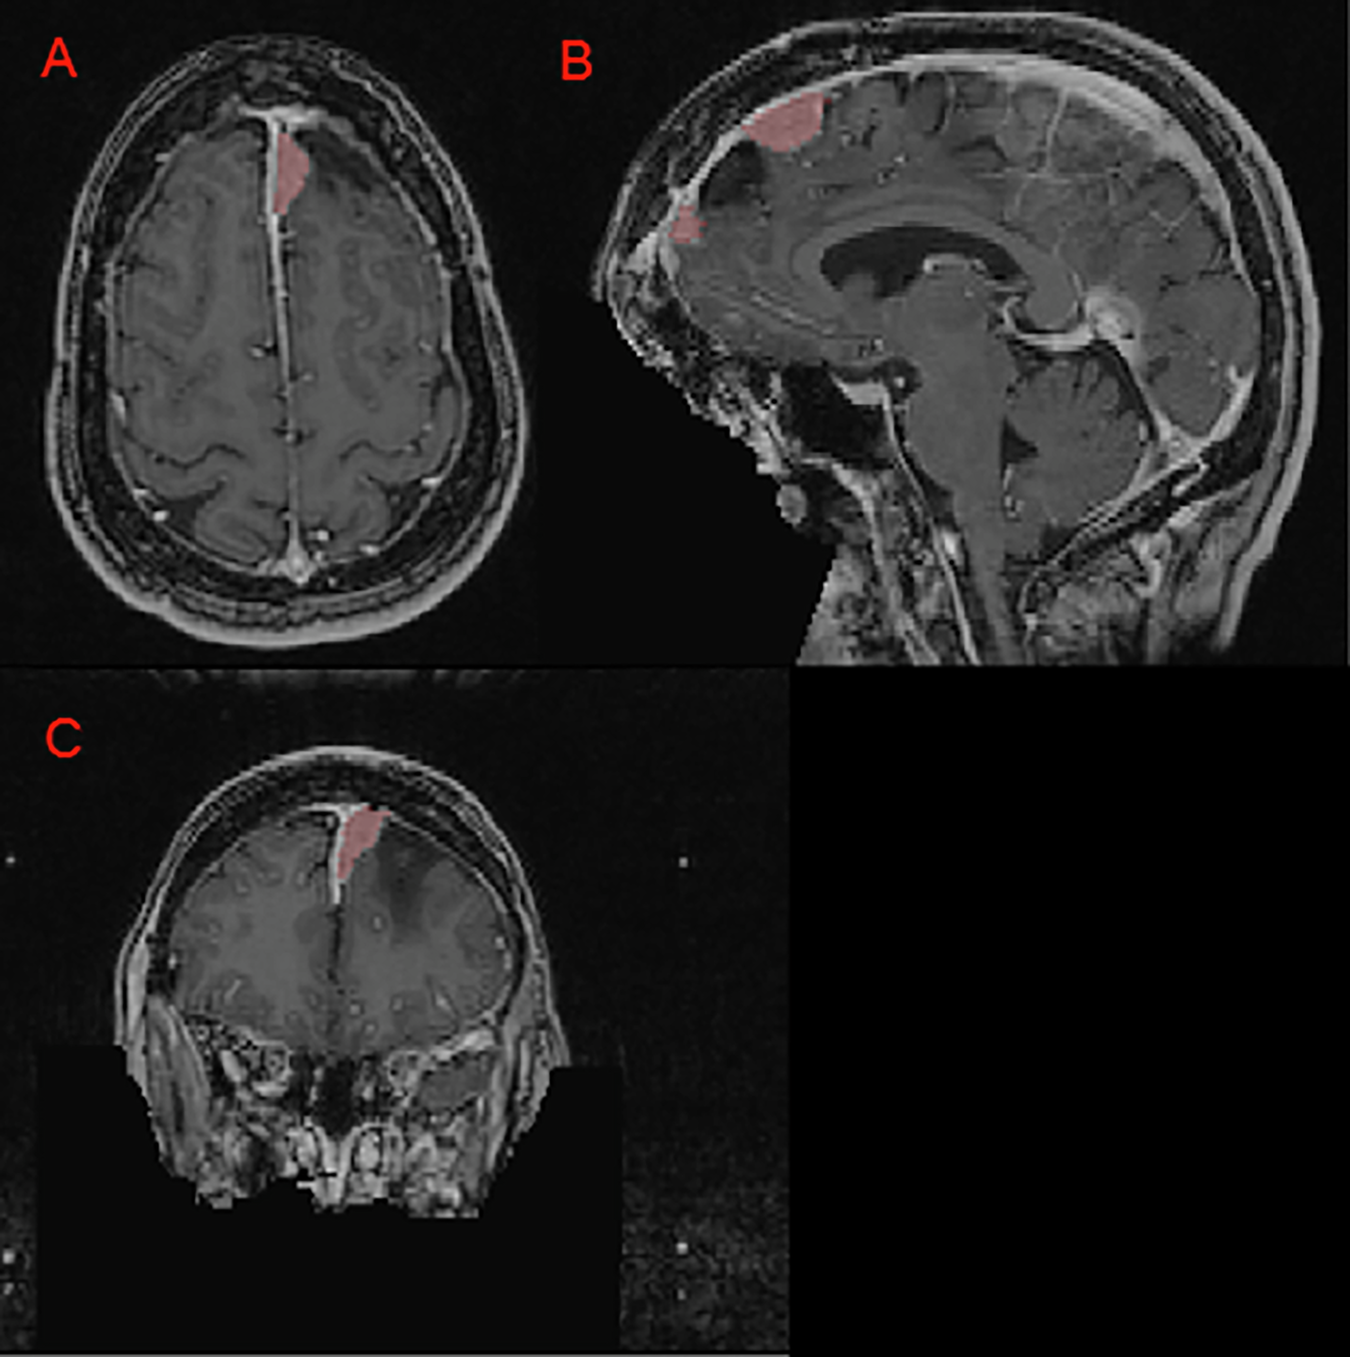

Panels A, B, and C depict a left anterior falcine meningioma (red) on axial, sagittal, and coronal images respectively. Panel B demonstrates an area of hypointense encephalomalacia between two separate anterior falcine meningioma components. Panels B and C highlight the defacing process, which removes pixels in and around the face to eliminate potentially identifying facial features.